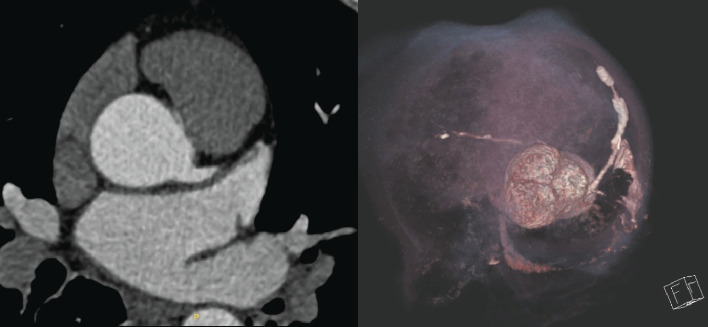

A 67-year-old male presented with non-ST elevation myocardial infarction (NSTEMI) with underlying anomalous origin of the right coronary artery (RCA) and a malignant course between the aorta and pulmonary artery. Previous CABG with LIMA and RIMA grafts had failed, leaving the patient with severe in-stent restenosis (ISR) in the LAD and degenerated, blocked grafts. The patient underwent percutaneous coronary intervention (PCI) to the anomalous RCA, which posed challenges in engagement due to its anomalous course. This case report discusses the complexities of managing such anatomies, emphasizing the role of CT coronary angiography, the difficulty of engaging anomalous arteries, and the techniques used to achieve successful PCI.